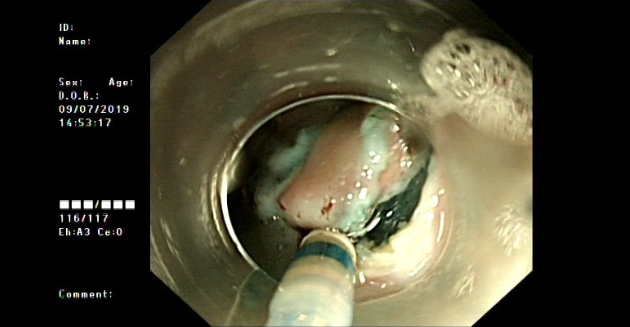

The patient had no contraindication to surgery for the examinations and endoscopic submucosal dissection (ESD) was performed. (Figure 5)